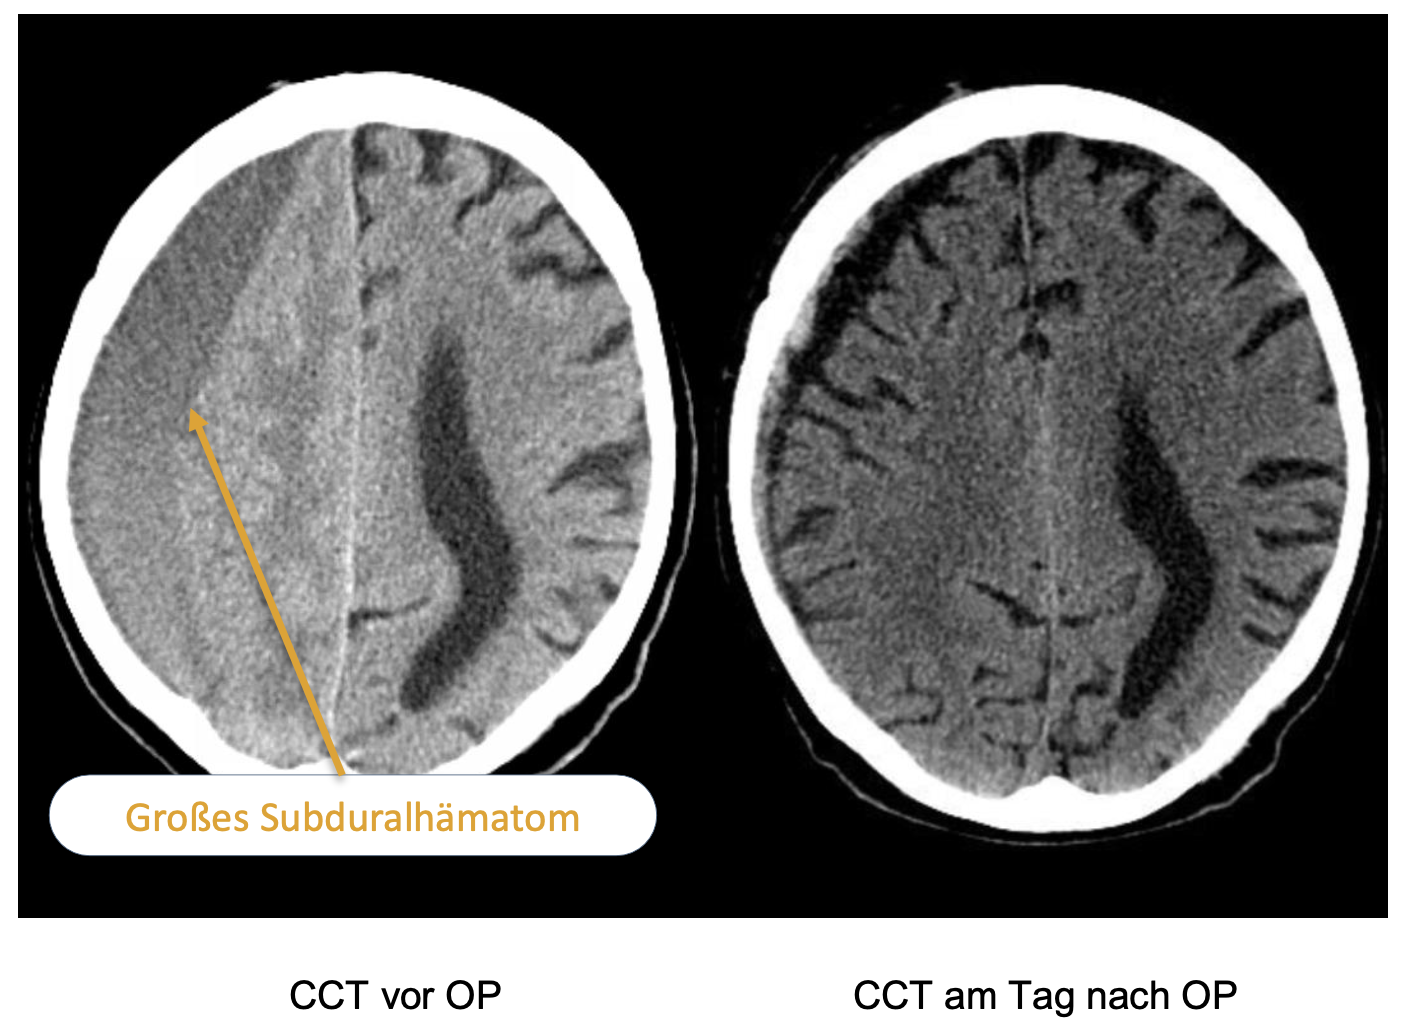

Patient 3 (Subduralhämatom)

Drei Tage nach der zweiten Patientin wird uns aus dem Schwesterkrankenhaus ein bislang sehr rüstiger über 90-jähriger Patient zuverlegt. Er hatte in den letzten Tagen und Wochen unter einer OAK mit Edoxaban eine zunehmende Hemiparese links entwickelt.

In der CCT hatte sich ein großes chronisches Subduralhämatom mit erheblicher raumfordernder Wirkung gezeigt. Es erfolgt die Bohrlochtrepanation. In der Folge ist die Symptomatik komplett rückläufig, der Patient konnte eine Woche nach der OP beschwerdefrei in die ambulante Weiterbehandlung entlassen werden.